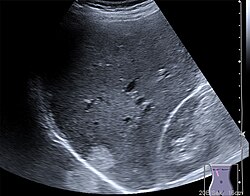

B-Mode (B für englisch brightness modulation) ist eine andere Darstellung der Information des Amplituden-Modus, bei der die Echointensität in eine Helligkeit umgesetzt wird. Durch mechanisches Bewegen der Sonde überstreicht der Messstrahl eine Fläche in einer Ebene ungefähr senkrecht zur Körperoberfläche. Der Grauwert eines Bildpunktes auf dem Bildschirm ist ein Maß für die Amplitude eines Echos an dieser Stelle.

2D-Echtzeitmodus (2D-realtime)

Im 2D-Echtzeitmodus, der derzeit häufigsten Anwendung des Ultraschalls, wird ein zweidimensionales Schnittbild des untersuchten Gewebes durch automatische Verschwenkung des Messstrahls und Synchronisierung der B-mode- Darstellung in Echtzeit erzeugt. Das Schnittbild wird dabei aus einzelnen Linien zusammengesetzt, wobei für jede Linie ein Strahl ausgesendet und empfangen werden muss. Die Form des erzeugten Bildes hängt dabei vom eingesetzten Sondentyp ab. Der 2D-Echtzeitmodus kann mit anderen Verfahren wie dem M-Mode oder der Doppler-Sonografie gekoppelt werden. Je nach Eindringtiefe und Sondentyp können nur einige wenige oder bis zu über hundert zweidimensionale Bilder pro Sekunde dargestellt werden.